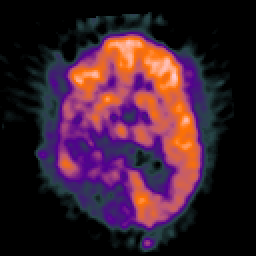

Glioma Overlay -- Slice #11

[Home][Help][Clinical] Slice 11